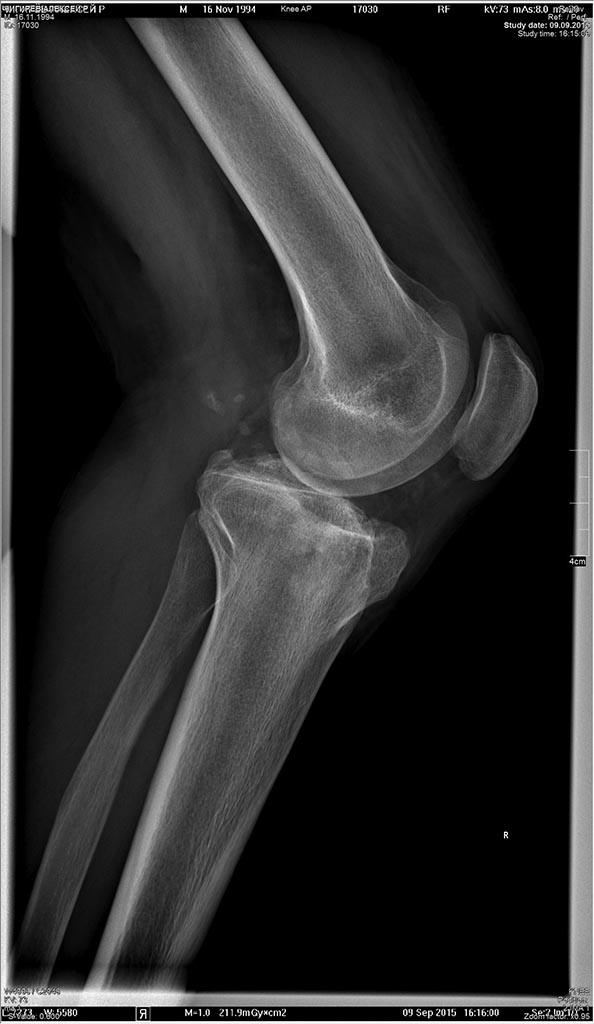

Пациент 21 г.посттравматический гонартроз. Застарелое повреждение наружной боковой и задней крестообразной связок. Посттравматическая нейропатия малоберцового нерва.

Травма 3 года назад.

Вывих костей голени.

Лечение консервативное. Два года назад ревизия малоберцового нерва-без эфaекта.

На момент осмотра: Жалобы на нестабильность в коленном суставе. Объем движений в коленном суставе полный. Нестабильность наружно-задняя.Р-гр в приложении.

Планируется первым этапом корригирующая остеотомия внутреннего мыщелкабольшеберцовой кости и восстановление наружной боковой связки.При необходимости вторым этапом пластика ЗКС.